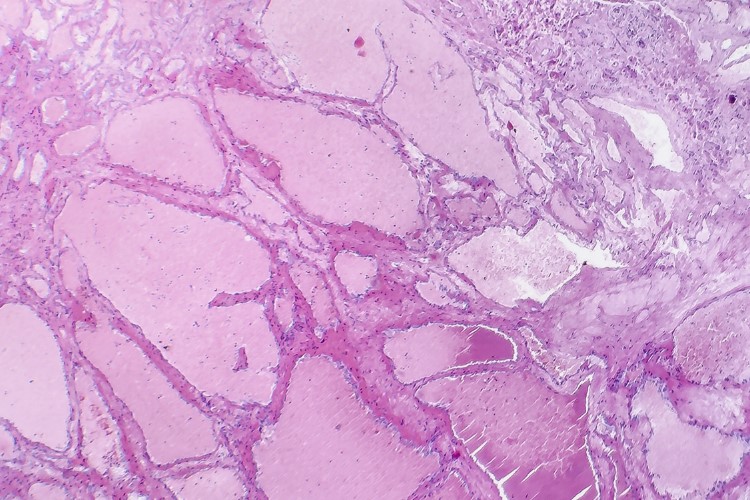

Отже, гемангіома — це доброякісна пухлина судинного походження. Щось ти чив? Він схожий на клубок судин, які зібралися разом утворюючи пухлину. Зазвичай зустрічається у немовлят чи маленьких діток, інколи в дорослих. Постає логічне питання: “Це небезпечно?”

Вони бувають різними. Ось вам короткий список для любителів класифікацій. Залежно від глибини ураження та виду судин, гемангіоми поділяються на:

- Поверхневі – зазвичай червоні та маленькі.

- Глибокі – менш видимі, але інколи небезпечніші.

- Змішані – ось тут потрібно бути особливо уважним, бо все цікаво и неоднозначно.